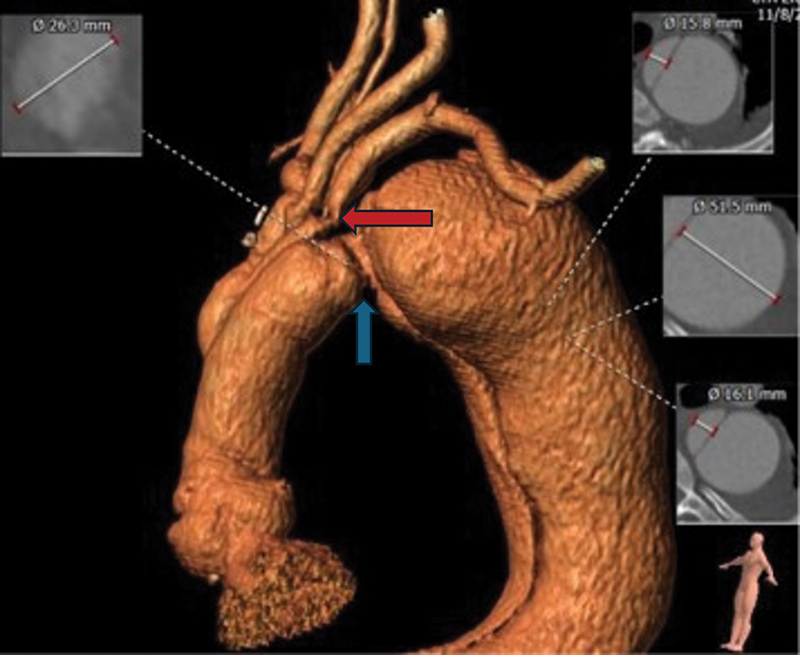

众所周知,脊髓缺血(SCI)是胸腹主动脉开放性和血管内修复术的并发症之一。围手术期增加脊髓灌注的措施,包括允许性高血压和放置腰椎引流管以控制脊髓压力,通常用于降低脊髓缺血的风险。围术期减少脊髓易受缺血性损伤的其他措施包括低体温、类固醇和输注纳洛酮。大多数病例会在手术后立即或数天内显现,并在采取上述措施后得到改善。我们描述了胸腔内血管主动脉瘤修复术后 20 个月出现延迟性 SCI 的罕见病例。

Spinal cord ischemia (SCI) is a well-known complication of both open and endovascular repair of the thoracoabdominal aorta. Perioperative maneuvers to increase spinal cord perfusion, including permissive hypertension and lumbar drain placement to control spinal pressure, are commonly used to reduce the risk of SCI. Additional perioperative measures to reduce the susceptibility of the spinal cord to ischemic insult include hypothermia, steroids, and naloxone infusion. Most cases manifest immediately or within days of surgery and improve with the aforementioned maneuvers. We describe a rare occurrence of delayed SCI 20 months after thoracic endovascular aortic aneurysm repair.